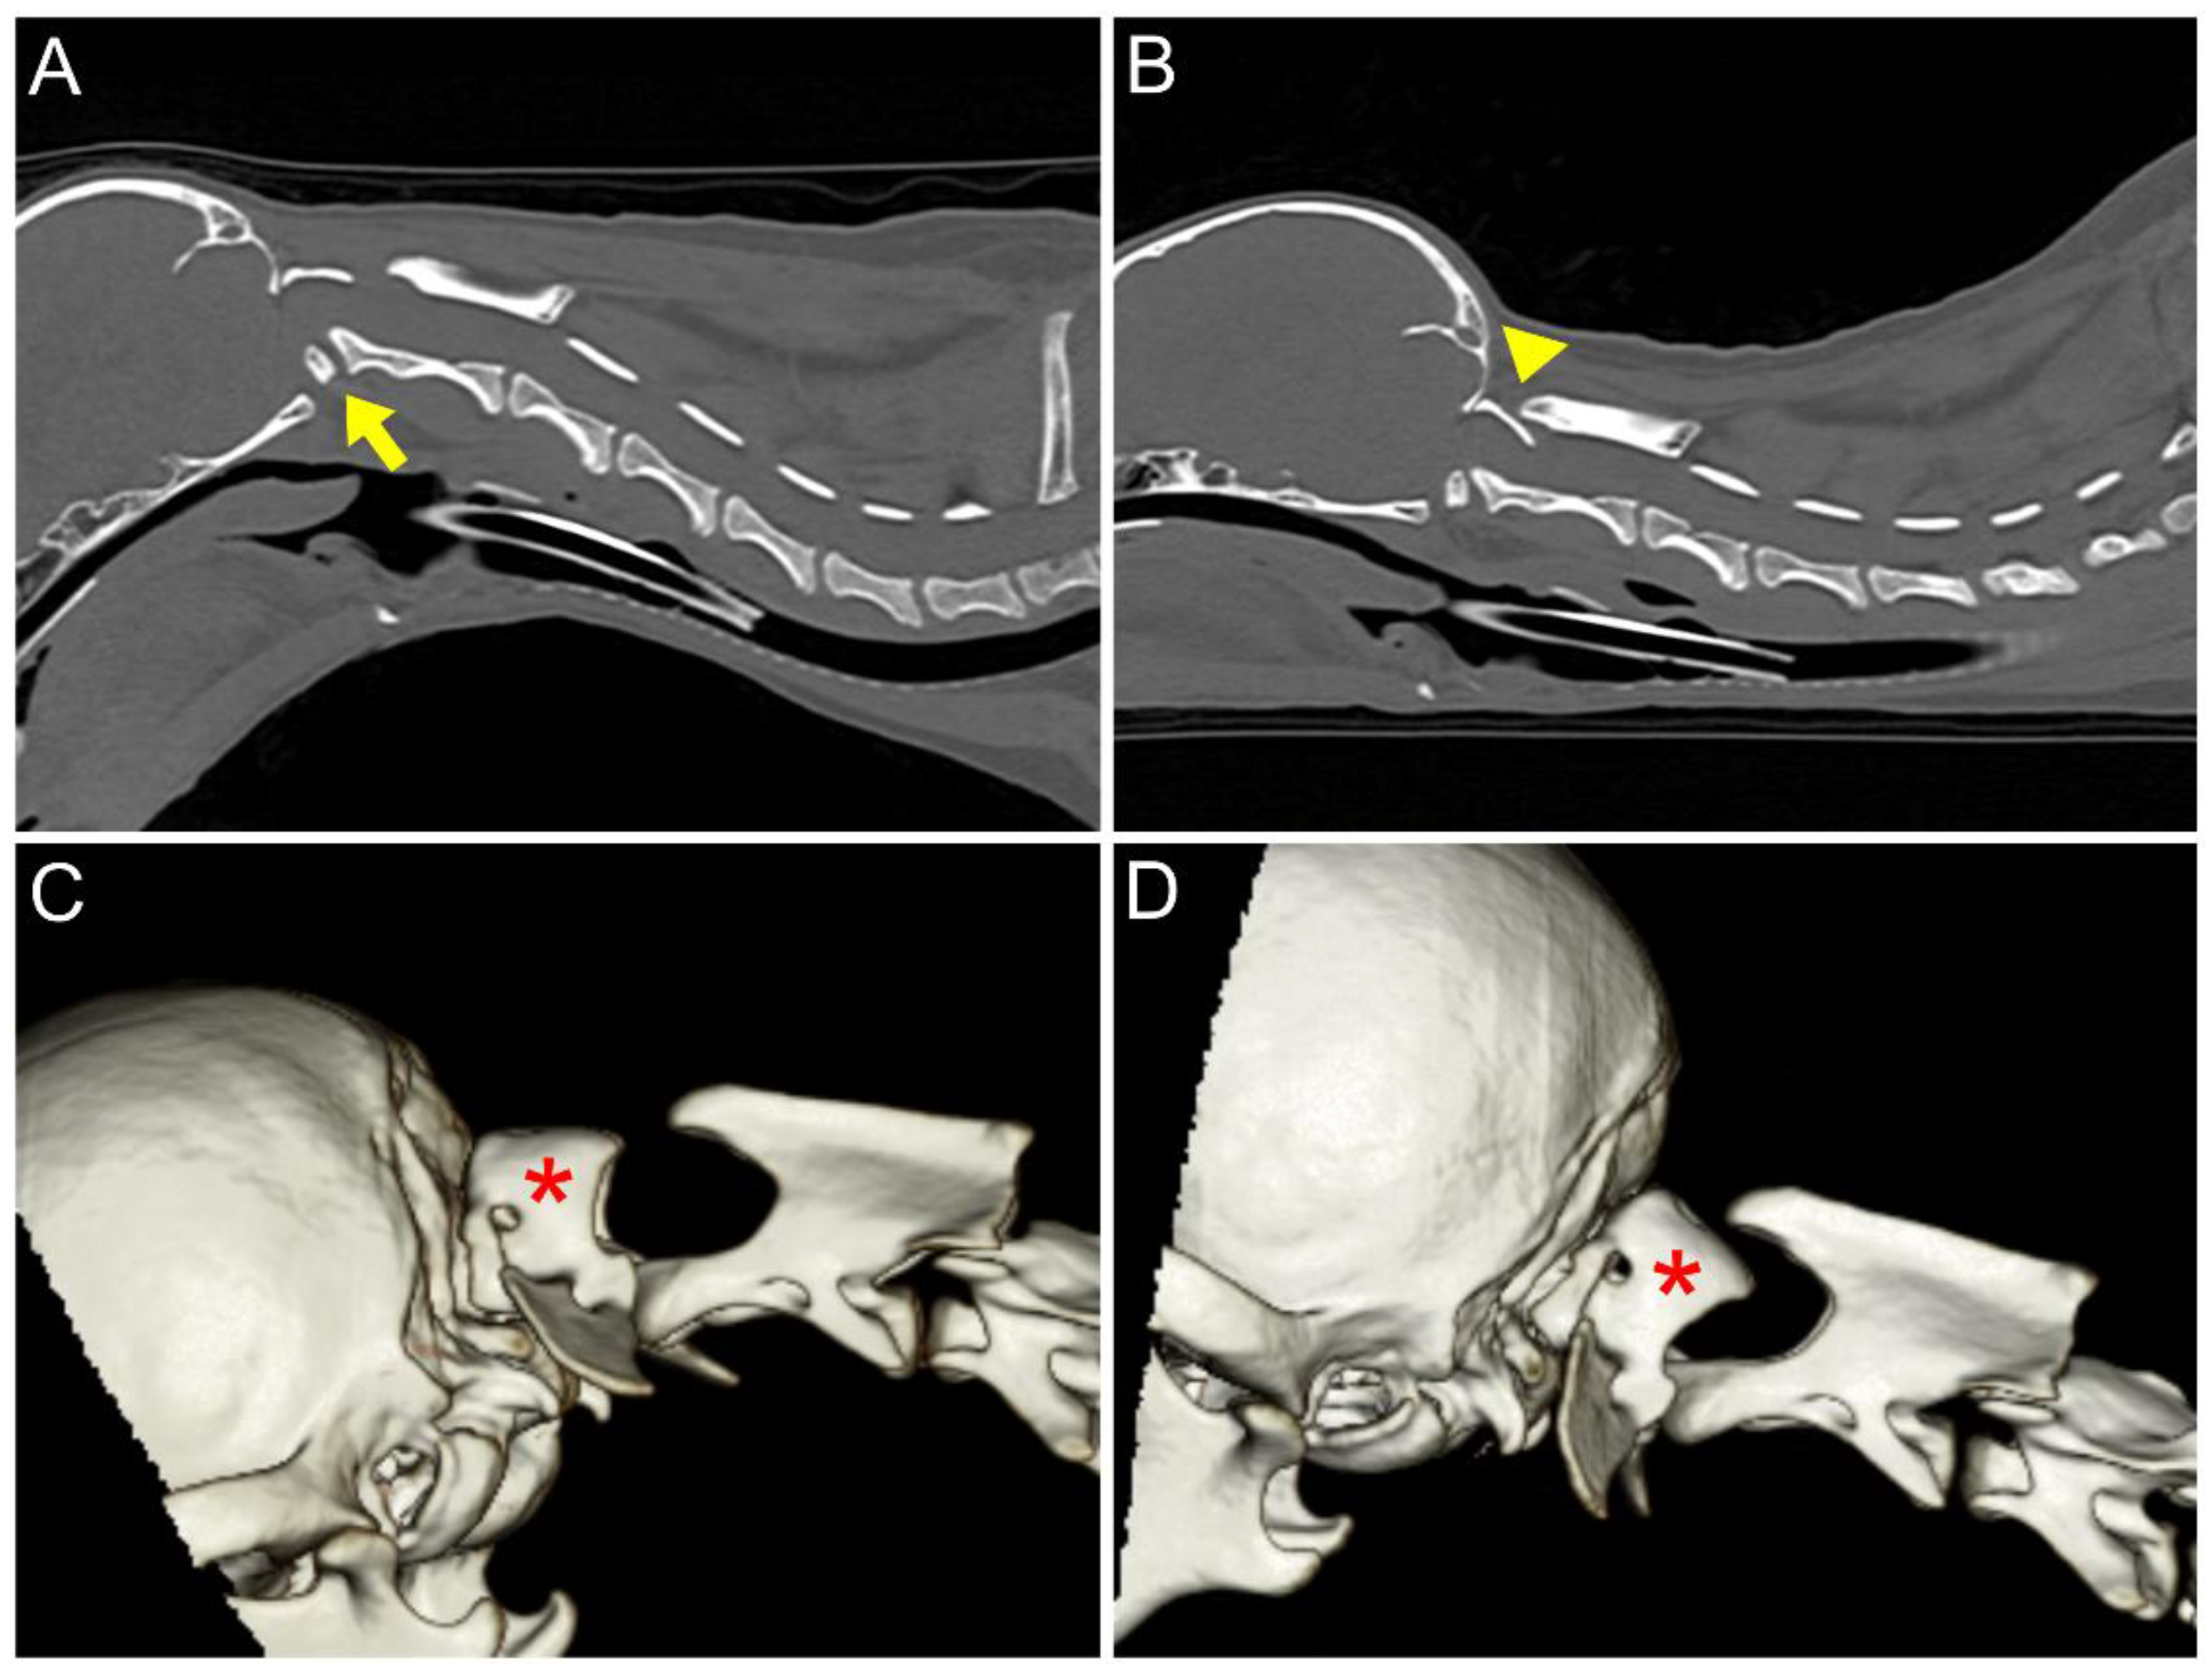

2. Case Description